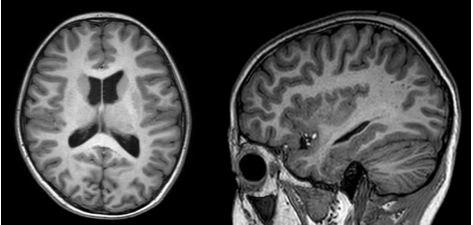

第三步:影像学检查

头颅磁共振检查可以直观呈现大脑结构,评估是否存在脑血管病变或早期萎缩,为制定干预方案提供重要依据。